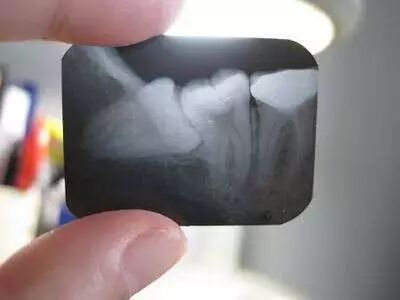

1、龋齿和牙髓炎

由于孕妈妈们的饮食习惯、激素分泌及代谢水平的变化,比其他人更容易患龋齿,会影响咀嚼功能,降低各种营养元素的摄入量。

当深龋进一步发展到牙髓炎时,便会导致牙齿疼痛,甚至是面部肿痛,严重影响生活质量,最终可能导致胎儿的生长发育,同时也可能会影响胎儿的牙齿发育及钙化。怀孕牙疼有蛀牙等口腔问题怎么办?添加口腔专家微信BT18181883772,在线一对一给您专业建议,免受牙痛之苦。

怀孕前保持良好的口腔卫生,养成定期口腔检查的习惯,发现问题尽早解决,不让牙齿疾病给孕妈妈带来不良影响。如果怀孕期间看牙,首先要告知医生自己已经怀孕了,因为孕期是不建议做X线检查的,除非极为特殊的情况。